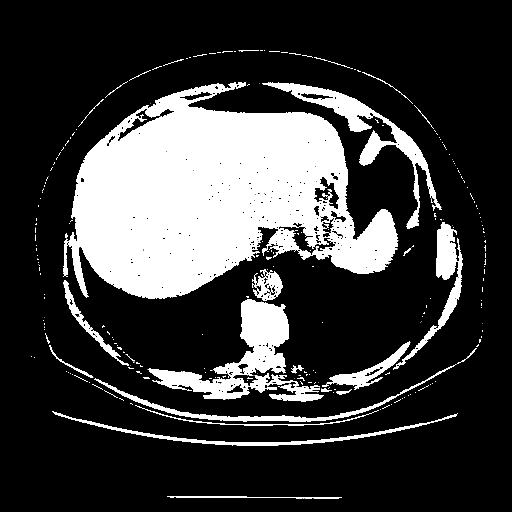

Reconstructed NATIVE CT scan (cycle consistency)

Full window (WL 1023.5, WW 4095 β†’ Low βˆ’1024, High +3071)

Actual HU range: [-1024.0, 3071.0]